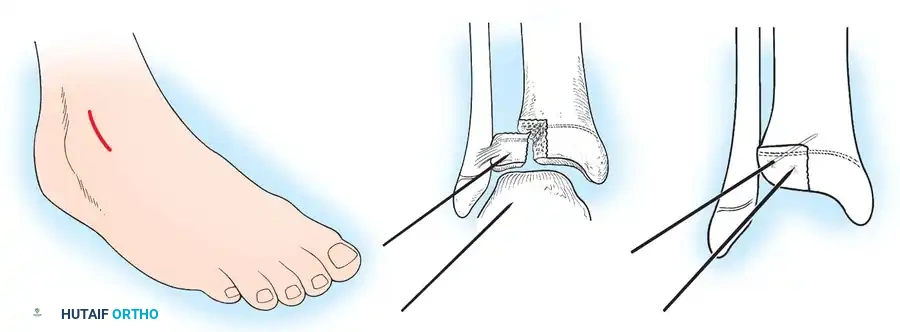

2. Surgical Approach:

* Make a longitudinal medial or lateral parapatellar incision, dictated by the primary location of the fracture line.

* Carry the dissection through the subcutaneous tissues down to the fracture site. Expose the fracture widely, but preserve the periosteal attachments to the anterior fragment to maintain vascularity.

5. Fixation:

* For vertical fracture components, insert transverse guide pins.

* In older children and adolescents nearing skeletal maturity, utilize 4.0mm or 4.5mm partially threaded cancellous bone screws to achieve interfragmentary compression.

* In younger children with significant remaining growth potential, utilize smooth Kirschner wires (K-wires) placed transversely or horizontally to minimize the risk of physeal arrest.

Placement of transverse fixation pins.

Final construct utilizing cancellous screws for rigid fixation.